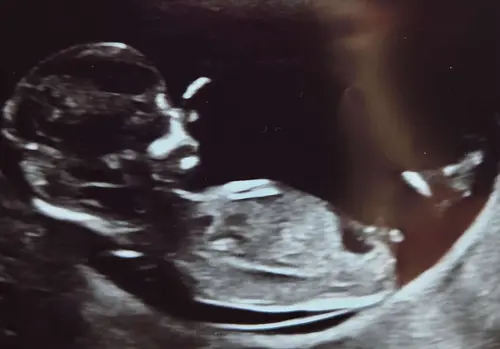

Vandaag 12+5. Ik heb vandaag de 13 weken echo gehad. Ik denk een meisje, wat denken jullie?

Het geslacht is niet helemaal duidelijk te zien, dus het zou zo goed een meisje als jongen kunnen zijn. Maar ik gok een meisje! 馃

Ik denk meisje. Bij jongen zou het volgens mij echt meer naar boven moeten steken.

Jaaa ik raak zoo zenuwachtig hahaha maar dat heb je met die theorie毛n natuurlijk. Ik zie zelf idd ook meisjes nub

Jaa dat zei de verloskundige idd maar ik denk idd dan veen ervoor. Heb 1 waar je hem helemaal ziet. Theorie毛n blijven lastig 馃き馃槀

Die zegt jongen maar dat klopte bij mijn eerste ook niet haha, dus die geloof ik nooit zo

Waar kijk je precies naar? Ik dacht dat de nub dan altijd naar boven moest steken, ik snap het niet meer haha. Toch maar wachten tot de geslachtsecho